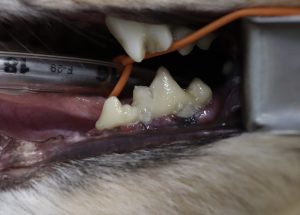

こちらの患者様は半年前に全身麻酔下で歯科処置を行い、写真の歯(右上顎第四前臼歯)に歯周組織再生治療を行いました。

患者様の献身的な通院もあり、術後2~3ヶ月は安定していたですが、その後の歯周病の進行により歯肉が後退し歯根が露出しています。

可能であれば機能歯(犬歯や大臼歯などの日常生活で犬が使用する歯)を残してあげたいというご希望もございましたが、

1回目の再生治療が奏功せず結果的に抜歯処置となりました。